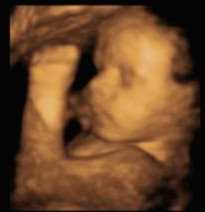

Vika 28

Lungun nálgast nú fullan þroska. Hreyfing öndunarfæra eru nú í takt og spila vel saman. Ef barnið er karlkyns færast eistu niður í pung. Barnið er nú 35 cm langt og 1,15 kg.

Myndir